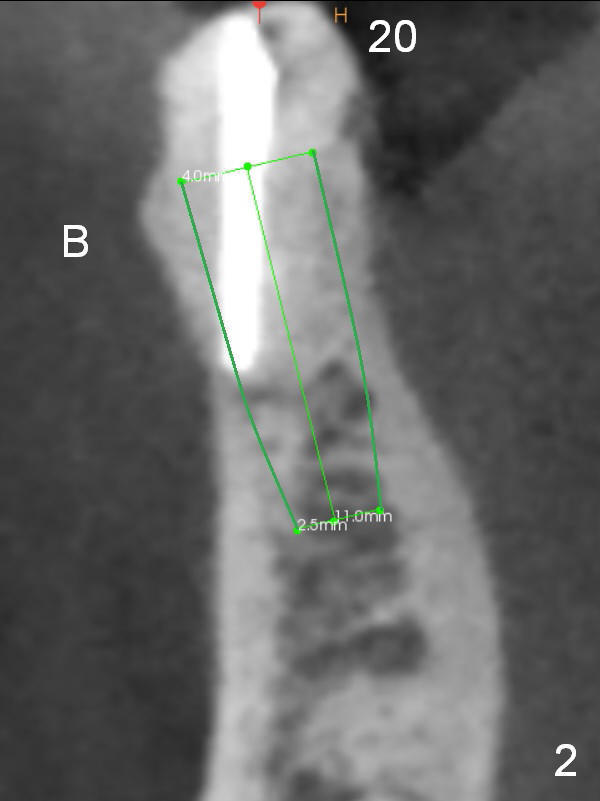

A 71-year-old man requests restoration at #18-20 (Fig.1). Placing implants at the narrow ridge of the sites of #18 and 19 is quite challenging (Fig.3,4), as compared that at #31 (Fig.5). Since the bone density at the crest is high (1200-1500 u), use a surgical high speed fissure bur for sectioning the crest, followed by BEB at 11 mm. It appears safer to place 1-piece implant (Fig.3) than 2-piece one (Fig.4). Since the total mesiodistal distance for #18-20 is 18 mm, splinting the three-units should be a sound treatment option.

After removing the residual root at #20, no antibiotic will be used for socket disinfection except gauze. It seems that an implant smaller than 4 mm is needed (Fig.1,2).